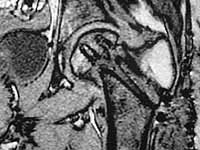

I would leave it as it is. Because surgical intervention will not be able to prevent osteonecrosis if it is going to be. MRI may be helpful to determine union if there is any and also gives an idea about the viability of the head.

establish vascular status via mri and if viable follow with proximal valgus osteotomy

I think that this 31 yo deserves a try with valgus osteotomy, as so nicely illustrated by stephen kottmeier. However, I'd do it no matter what an MRI shows - thus why bother with the MRI? (What sort of data support MRI's ability to predict segmental collapse?)